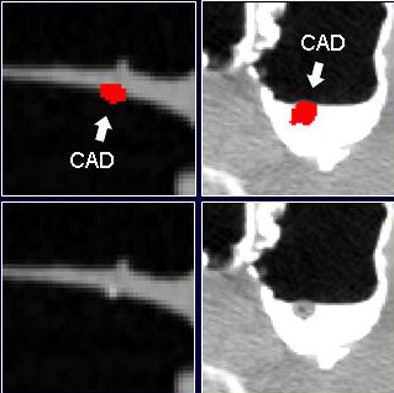

![]()  |

| Before the application of the densitometric partial-volume correction and wall-connection analysis (top row) in virtual colonoscopy data, CAD misinterprets residual fecal material as polyps. These false positives are eliminated after application of the two methods (bottom row). |